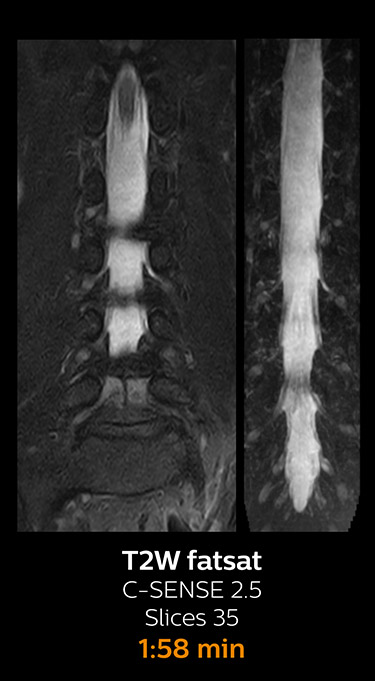

Fast MRI of cervical spine

With Compressed SENSE, the scan time for the routine cervical spine examination at KNC was reduced from 13:11 to 9:52 minutes, which corresponds to 25% reduction.

MRI examination of cervical spine with Compressed SENSE

MRI examination of the cervical spine with Compressed SENSE

Ingenia 3.0T CX

Scan time 9:52 min. (was 13:11 min. without Compressed SENSE)